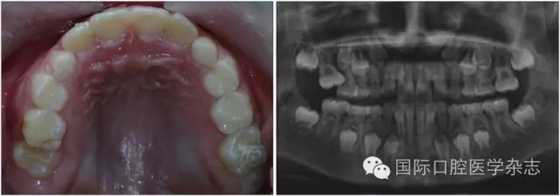

左:口內照;右:全景片。

圖7 左上第一恒磨牙異位萌出,左上第二乳磨牙松動

Fig 7 Ectopic eruption ofleft upper the first permanent molar, loose of left upper the second primarymolar

牙齒異位萌出是指恒牙在萌出過程中,未在牙列的正常位置萌出,兒童口腔臨床最常見的是上頜第一恒磨牙和上頜尖牙的異位萌出。造成第一恒磨牙異位萌出的原因包括:第二乳磨牙和第一恒磨牙的牙冠體積較大;頜骨的發(fā)育不足,尤其是上頜結節(jié)發(fā)育不足;第一恒磨牙的萌出角度異常,牙軸向近中傾斜等,歸根結底是在第一恒磨牙萌出階段出現了牙量和骨量不調的問題,頜骨發(fā)育不足是最主要的原因。發(fā)生率為2%~6%,男性多于女性,其中2/3發(fā)生在上頜,可單側或雙側對稱出現。第一恒磨牙的異位萌出常常造成第二乳磨牙早失,牙弓長度減小。臨床上,常用分牙簧分離第一恒磨牙與第二乳磨牙,或使用恒磨牙面粘著舌扣的Halterman矯治器,或變異Nance弓推第一恒磨牙向遠中的方法,改變恒牙萌出道,阻斷恒磨牙對乳磨牙的壓迫吸收,引導恒磨牙正常萌出。圖7顯示為一左上第一恒磨牙異位萌出的患兒,左上第二乳磨牙松動,牙弓長度減少[6]。